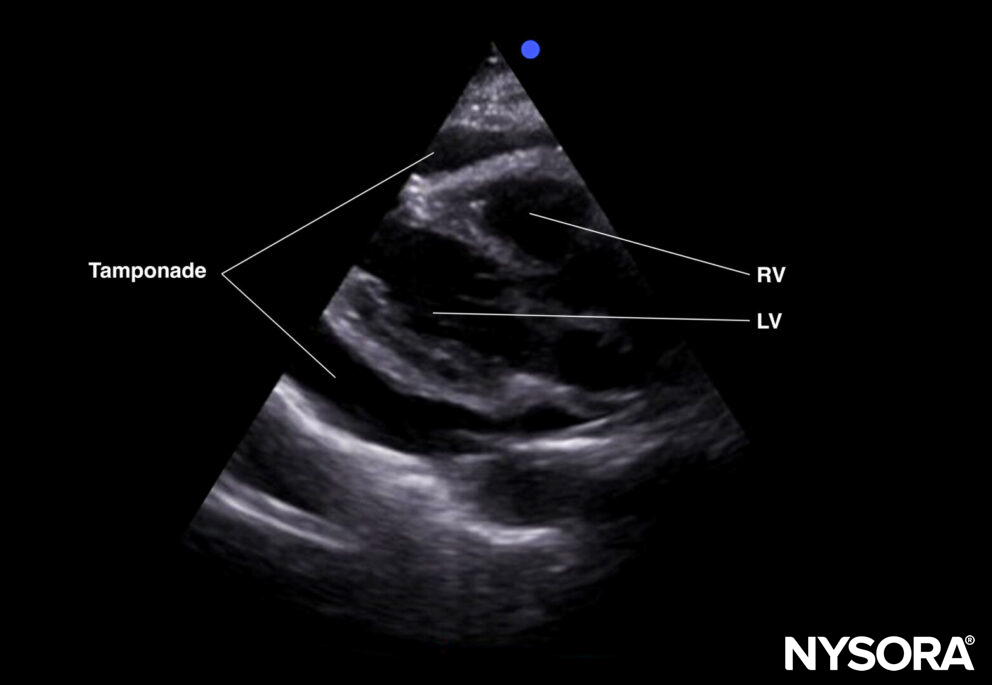

- The subcostal four-chamber view is excellent to rule out tamponade. In the presence of a tamponade, the heart is surrounded by an anechoic layer. More info on tamponade can be found in the cardiac category.

Subcostal four-chamber view of a tamponade.